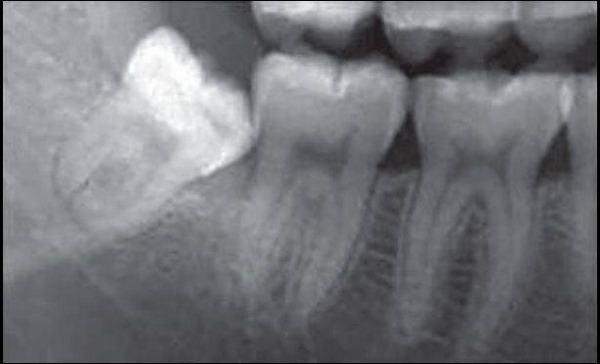

智齿的专业名词是第三磨牙,是恒牙中最后萌出的牙齿。一般在18岁以后才萌出,口腔内上下左右共4颗。现代人中长了一个以上智齿的占68.2%,其中下颌智齿的阻生率较高,约为52.3%。阻生智齿不能整齐排列于牙列中,会倾斜生长,易与旁边牙齿形成缝隙。再加上牙缝间容易存留食物残渣,这就为细菌生长繁殖制造了有利条件,从而容易造成智齿和邻近牙齿的龋坏以及智齿冠周的牙龈红肿。

今年大三的小许同学也是因为饱受智齿折磨,才下决心拔掉智齿。此前小许发现自己右下长了阻生智齿,并将前面的大牙给顶坏了,她去到医院将大牙补好后医生建议她把智齿也拔掉,但因为害怕拔牙,小许觉得反正智齿也不疼并没有听医生的建议。

北京维乐口腔医院张骞主任表示:“大部分生有智齿的人都会面临像小许这样的困扰,智齿不能完全萌出,其牙冠常被牙龈覆盖住一部分。这个开口就像是扁扁的口袋,学名冠周袋,在进食的过程中,很容易积存食物残渣。”这里有适宜的温度、湿度和食物供给,简直就是细菌的乐园,它们尽情造作的结果就是智齿容易遭遇龋坏和反复的发炎。

大多数人认为智齿不疼就可以不用管了,但即使智齿暂时不疼,也不要大意,它可能引发多种问题。容易滋生细菌、引发龋齿、牙冠损伤、造成牙齿不整齐的现象。而且,阻生的智齿往往不能与对颌牙齿建立正常的咬合关系,长时间可导致颞下颌关节弹响、牙合疼痛,夜磨牙等症状,对青壮年的身心健康影响较大。